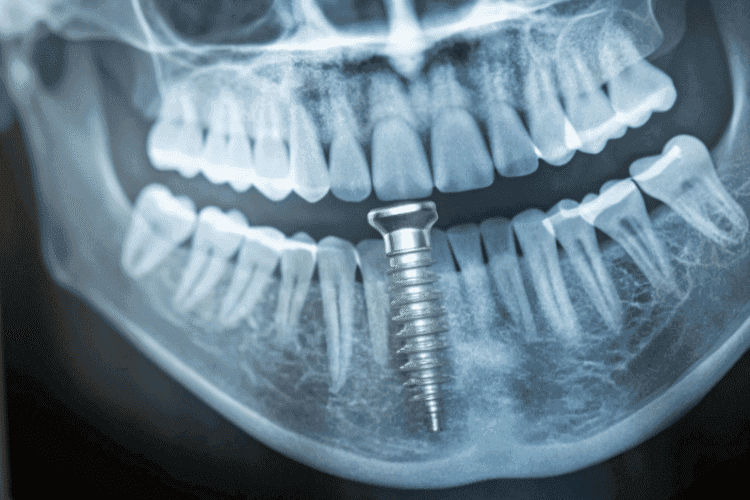

Dental implants are a type of tooth replacement that act as artificial tooth roots. In a surgical procedure, a practitioner (oral surgeons, periodontists, or experienced general dentists) inserts an implant into your jawbone. Implants are a sturdy foundation for crowns, bridges, or full-arch dentures.

Through a process called osseointegration, the implant fuses with your bone, becoming a permanent part of your mouth. This fusion helps create a natural look and feel, so your new tooth functions just like your original one. Hence, dental implants are a restorative dentistry procedure.

- Implant post: A small titanium screw placed into the jawbone to replace the tooth root.

- Abutment: A connector that attaches to the implant post and supports the replacement tooth.

- Crown/bridge/denture: The visible part of the restoration that looks and functions like a natural tooth.

Together, these components create a strong and natural-looking tooth replacement solution.